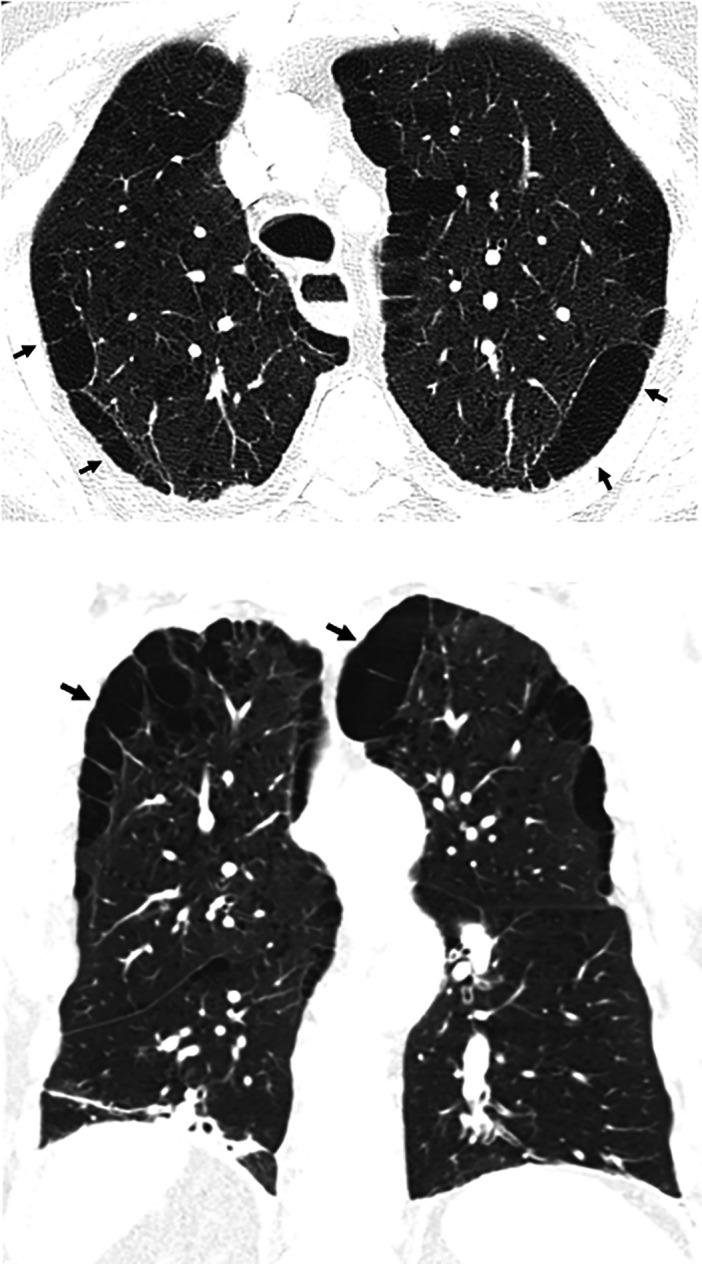

This American Thoracic Society, European Respiratory Society, Japanese Respiratory Society, and Asociación Latinoamericana de Tórax guideline updates prior idiopathic pulmonary fibrosis (IPF) guidelines and addresses the progression of pulmonary fibrosis in patients with interstitial lung diseases (ILDs) other than IPF. A committee was composed of multidisciplinary experts in ILD, methodologists, and patient representatives. ) Update of IPF: Radiological and histopathological criteria for IPF were updated by consensus. Questions about transbronchial lung cryobiopsy, genomic classifier testing, antacid medication, and antireflux surgery were informed by systematic reviews and answered with evidence-based recommendations using the Grading of Recommendations, Assessment, Development and Evaluation (GRADE) approach. ) Progressive pulmonary fibrosis (PPF): PPF was defined, and then radiological and physiological criteria for PPF were determined by consensus. Questions about pirfenidone and nintedanib were informed by systematic reviews and answered with evidence-based recommendations using the GRADE approach. ) Update of IPF: A conditional recommendation was made to regard transbronchial lung cryobiopsy as an acceptable alternative to surgical lung biopsy in centers with appropriate expertise. No recommendation was made for or against genomic classifier testing. Conditional recommendations were made against antacid medication and antireflux surgery for the treatment of IPF. ) PPF: PPF was defined as at least two of three criteria (worsening symptoms, radiological progression, and physiological progression) occurring within the past year with no alternative explanation in a patient with an ILD other than IPF. A conditional recommendation was made for nintedanib, and additional research into pirfenidone was recommended. The conditional recommendations in this guideline are intended to provide the basis for rational, informed decisions by clinicians.

美国胸科学会、欧洲呼吸学会、日本呼吸学会和拉丁美洲胸科学会更新了特发性肺纤维化(IPF)指南,涵盖了除 IPF 以外的间质性肺疾病(ILD)患者肺纤维化的进展。一个委员会由ILD 的多学科专家、方法学家和患者代表组成。

• 更新 IPF:通过共识更新了 IPF 的放射学和组织病理学标准。关于经支气管肺冷冻活检、基因组分类器检测、抗酸药物和抗反流手术的问题,通过系统评价提供信息,并使用基于证据的推荐和 Grading of Recommendations, Assessment, Development and Evaluation (GRADE) 方法回答。

• 进行性肺纤维化(PPF):定义了 PPF,然后通过共识确定了 PPF 的放射学和生理学标准。关于吡非尼酮和尼达尼布的问题,通过系统评价提供信息,并使用基于证据的推荐和 GRADE 方法回答。

• 更新 IPF:有条件建议将经支气管肺冷冻活检视为具有适当专业知识的中心替代外科肺活检的可接受方法。未对基因组分类器检测提出建议或反对。有条件反对使用抗酸药物和抗反流手术治疗 IPF。

• PPF:PPF 定义为在过去一年中,在非 IPF 的ILD 患者中,出现至少三个标准中的两个(症状恶化、放射学进展和生理学进展),且无其他解释。建议使用尼达尼布,并建议对吡非尼酮进行进一步研究。